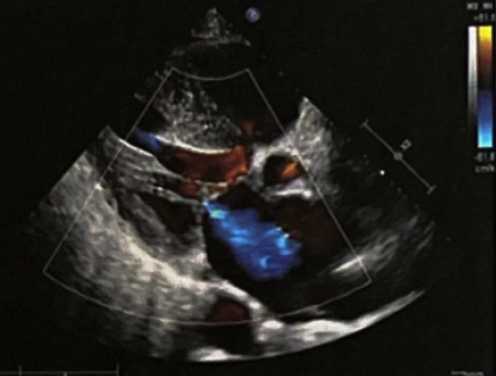

◆超声心动图:左心房、右心房扩大(LA5.1cm,RA4.6cm);升主动脉增宽;主动脉瓣中度反流;二尖瓣中度反流;三尖瓣中度反流;室间隔增厚;心律失常(图2)。

.png)

图2. 超声心动图